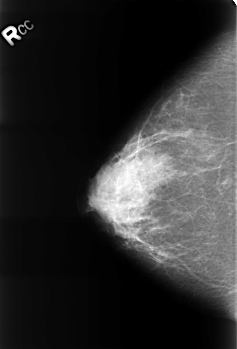

B_3243_1.RIGHT_MLO

RIGHT_CC LINES 4528 PIXELS_PER_LINE 3080 BITS_PER_PIXEL 12 RESOLUTION 50 NON_OVERLAY

RIGHT_MLO LINES 4480 PIXELS_PER_LINE 3064 BITS_PER_PIXEL 12 RESOLUTION 50 NON_OVERLAY